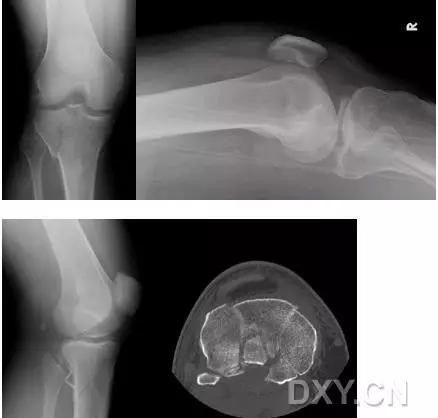

5. Hoffa 骨折

指股骨远端冠状面的骨折。

病例 1:一般股骨髁间、髁上粉碎骨折中含 Hoffa 骨折的不少见,但单纯后髁骨折则很少见。

正位片

侧位片

水平位 CT

第 2 例

第 3 例